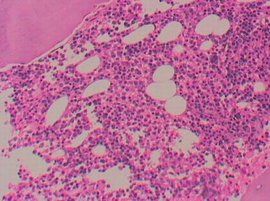

按白血病細胞成熟障礙阻滯階段,可將白血病分為急性、慢性兩種。急性白血病,白血病細胞成熟障礙阻滯在較早階段,病變細胞分化差,以原始、早期幼稚細胞為主,按FAB分型,包括急性淋巴細胞白血病和急性髓細胞白血病,自然病程多在半年以內。急性髓細胞白血病分為M0 — M7共8型,其中M0、M1、M2、M3屬於急性粒細胞白血病範疇。

M0:急性髓細胞白血病微分化型,原始粒細胞≥20%,形態學類似ALL-L2,無T、B淋巴系標記,至少表達一種髓系抗原,MPO陽性。

M1:急性髓細胞白血病未成熟型,原始粒細胞≥90%(NEC)。

M2:急性髓細胞白血病部分成熟型,分為M2a和M2b兩種類型。

M2a:原始粒細胞20~89%(NEC),早幼粒及以下階段粒細胞>10%,單核細胞<20%。

M2b:異常中幼粒細胞(核幼質老)≥20%(NEC)。

M3:急性早幼粒細胞白血病,異常早幼粒細胞≥20%,分為M3a(粗顆粒型)和M3b(細顆粒型)。